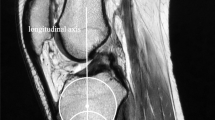

Bony posterior tibial slope

To ensure reliable and reproducible measurements, a standard protocol was applied by all observers. On a split screen the coronal, sagittal, and axial images were displayed, and the scout line and localizer mode were used to scroll through all three planes simultaneously. The annotation tools were then used to establish the centre of the tibial plateau on the axial image. The corresponding coronal image was defined as the reference image and the vertical intermediate line (yellow) defined the centre of the knee, dividing the tibial plateau into a medial and lateral half (Fig. 1). A second line (blue) was then drawn from the lateral to the medial border of the tibia, passing through the most inferior aspect of the tibial plateau. The annotation tools were then again used to establish the distance between the medial and lateral borders of the plateau. Parallel lines were drawn 25, 50, and 75% from the outer margin of the tibial plateau (Fig. 2). The corresponding sagittal images were used to measure both the bone and meniscal slopes in these three anatomic locations (Fig. 3). The proximal tibial anatomic axis (red line) was drawn by establishing two lines (blue lines), 2 and 4 cm distal to the joint line, and connecting the midpoint between these two lines (red line) (Fig. 3). The tibial plateau was marked with a line from the most anterior to the most posterior point of the tibial plateau (yellow line) (Fig. 3). The slope was measured between the tibial plateau (yellow line) and a line that was established 90° to the proximal tibial anatomic axis. If the slope was directed posteriorly it was defined as posterior or negative (−), and if the slope was directed anteriorly it was defined as anterior or positive (+).

The proximal tibial anatomic axis (PTAA) was established by drawing two lines on a sagittal image, 2 cm apart, from anterior to posterior (blue lines). The midpoint between these two lines was connected, resulting in a vertical line (red line) that is defined as the PTAA. The tibial plateau was defined by a line drawn from the most anterior to the most posterior point on a sagittal image (yellow line). An additional perpendicular line (green line) to the PTAA was drawn from the point where the tibial plateau line meets the PTAA. The angle between this line (green) and the tibial plateau line (yellow) has been defined as the posterior tibial slope. The slope was defined as posterior (−) if the plateau line is inferior to the perpendicular line, and anterior (+) if the plateau line is proximal to the perpendicular line